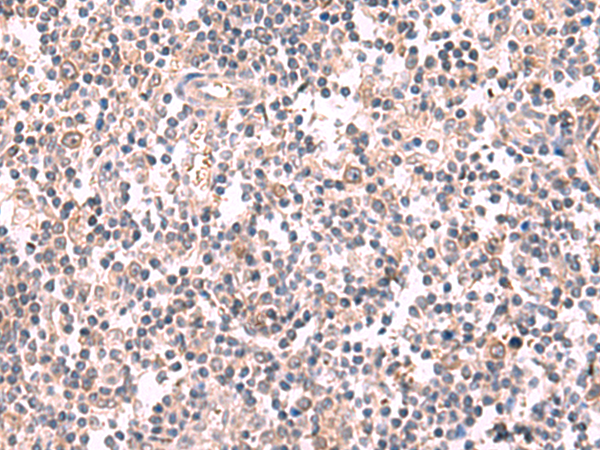

分类: 科研抗体货号: P10202别名: GST2; ERF3B应用: WB,IHC反应种属: Human, Mouse